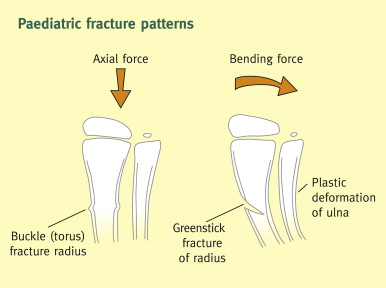

Buckle Fracture Symptoms Causes Treatment 2025, Buckle fracture of the wrist CUH 2025, Buckle Fracture Raleigh Hand Surgery Joseph J. Schreiber MD 2025, Fracture How to treat a buckle fracture of the distal radius 2025, Torus fracture Wikipedia 2025, Buckle fracture 2025, Kidshealth Buckle Fractures Akron Children s 2025, Buckle fractures of the distal radius in children CMAJ 2025, How to Care for Your Child with Buckle Fracture Sidra Medicine 2025, Kids Health Information Fracture care buckle injury 2025, The Pediatric Wrist Buckle Fracture is Common Louisville Bones 2025, Buckle fracture 2025, Forearm Fractures Children s Mercy Kansas City 2025, Buckle Fracture Raleigh Hand Surgery Joseph J. Schreiber MD 2025, Buckle Fractures Rady Children s Hospital 2025, Greenstick Buckle Fracture Activate Physiotherapy 2025, What are Buckle Fractures WristSupports 2025, Buckle Greenstick Fracture of the Distal Radius Sports 2025, Choosing Wisely Distal Radius Buckle Fractures CanadiEM 2025, Buckle Greenstick Fracture of the Distal Radius Sports 2025, Clinical Practice Guidelines Distal radius and or ulna 2025, Buckle fracture Radiology at St. Vincent s University Hospital 2025, Radiology Case 5 SpringerLink 2025, Buckle fracture of the wrist Resource Library Sheffield 2025, Forearm Fractures Children s Mercy Kansas City 2025, Buckle fracture Radiology Case Radiopaedia 2025, Fracture How to treat a buckle fracture of the distal radius 2025, Buckle fracture in a girl age 2 years 3 months who presented to 2025, Greenstick Fracture or Paediatric Fracture Treatment 2025, Buckle fracture Radiology Case Radiopaedia 2025, Buckle Fracture by Dr. David Nelson MD 2025, Pondering Paeds Buckle In 2025, State of the Art Pediatrics Buckle Fractures in Children 2025, OrthoKids Forearm Fractures 2025, Buckle Greenstick Fracture of the Distal Radius Sports 2025.

Buckle Fracture Symptoms Causes Treatment 2025, Buckle fracture of the wrist CUH 2025, Buckle Fracture Raleigh Hand Surgery Joseph J. Schreiber MD 2025, Fracture How to treat a buckle fracture of the distal radius 2025, Torus fracture Wikipedia 2025, Buckle fracture 2025, Kidshealth Buckle Fractures Akron Children s 2025, Buckle fractures of the distal radius in children CMAJ 2025, How to Care for Your Child with Buckle Fracture Sidra Medicine 2025, Kids Health Information Fracture care buckle injury 2025, The Pediatric Wrist Buckle Fracture is Common Louisville Bones 2025, Buckle fracture 2025, Forearm Fractures Children s Mercy Kansas City 2025, Buckle Fracture Raleigh Hand Surgery Joseph J. Schreiber MD 2025, Buckle Fractures Rady Children s Hospital 2025, Greenstick Buckle Fracture Activate Physiotherapy 2025, What are Buckle Fractures WristSupports 2025, Buckle Greenstick Fracture of the Distal Radius Sports 2025, Choosing Wisely Distal Radius Buckle Fractures CanadiEM 2025, Buckle Greenstick Fracture of the Distal Radius Sports 2025, Clinical Practice Guidelines Distal radius and or ulna 2025, Buckle fracture Radiology at St. Vincent s University Hospital 2025, Radiology Case 5 SpringerLink 2025, Buckle fracture of the wrist Resource Library Sheffield 2025, Forearm Fractures Children s Mercy Kansas City 2025, Buckle fracture Radiology Case Radiopaedia 2025, Fracture How to treat a buckle fracture of the distal radius 2025, Buckle fracture in a girl age 2 years 3 months who presented to 2025, Greenstick Fracture or Paediatric Fracture Treatment 2025, Buckle fracture Radiology Case Radiopaedia 2025, Buckle Fracture by Dr. David Nelson MD 2025, Pondering Paeds Buckle In 2025, State of the Art Pediatrics Buckle Fractures in Children 2025, OrthoKids Forearm Fractures 2025, Buckle Greenstick Fracture of the Distal Radius Sports 2025.